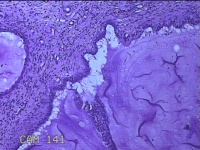

宫颈2点、3点、9点组织

性别

女

年龄

38岁

临床诊断

人乳头瘤病毒感染

一般病史

宫颈其他HPV12阳性

标本名称

大体所见

1.“宫颈2点组织”:灰白粉红色组织0.8x0.5x0.2cm一块。 2.“宫颈3点组织”:灰白粉红色组织0.7x0.5x0.2cm一块。 3.“宫颈9点组织”:灰白粉红色组织0.7x0.5x0.2cm一块。

图1